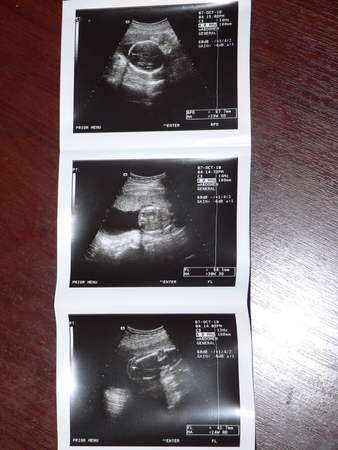

У НАС БУДЕТ ДЕВОЧКА... сказали - на 100%

Весим мы почти 600 гр., в головном предлежании (единственное головка низко, сказали, чуть больше лежать.. или бандаж), порок в развитии НЕТ (ттт), по размерам соответствуем 24 неделям....

Вот такие мы хорошие)))